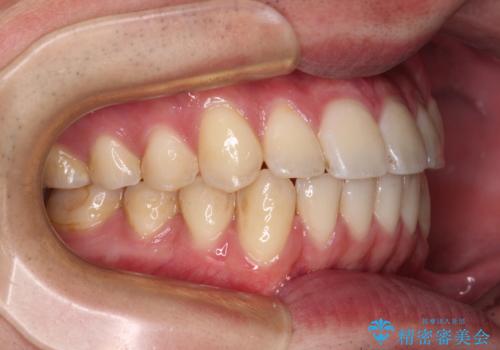

八重歯と前歯のクロスバイト ワイヤー装置で短期間矯正

上顎側切歯(前から2番目の歯)が内側に転位している歯列は、インビザラインでは排列が困難であることが多いため、期間を短く、より良い仕上がりとするため、ワイヤー装置にて矯正治療を行うこととしました。